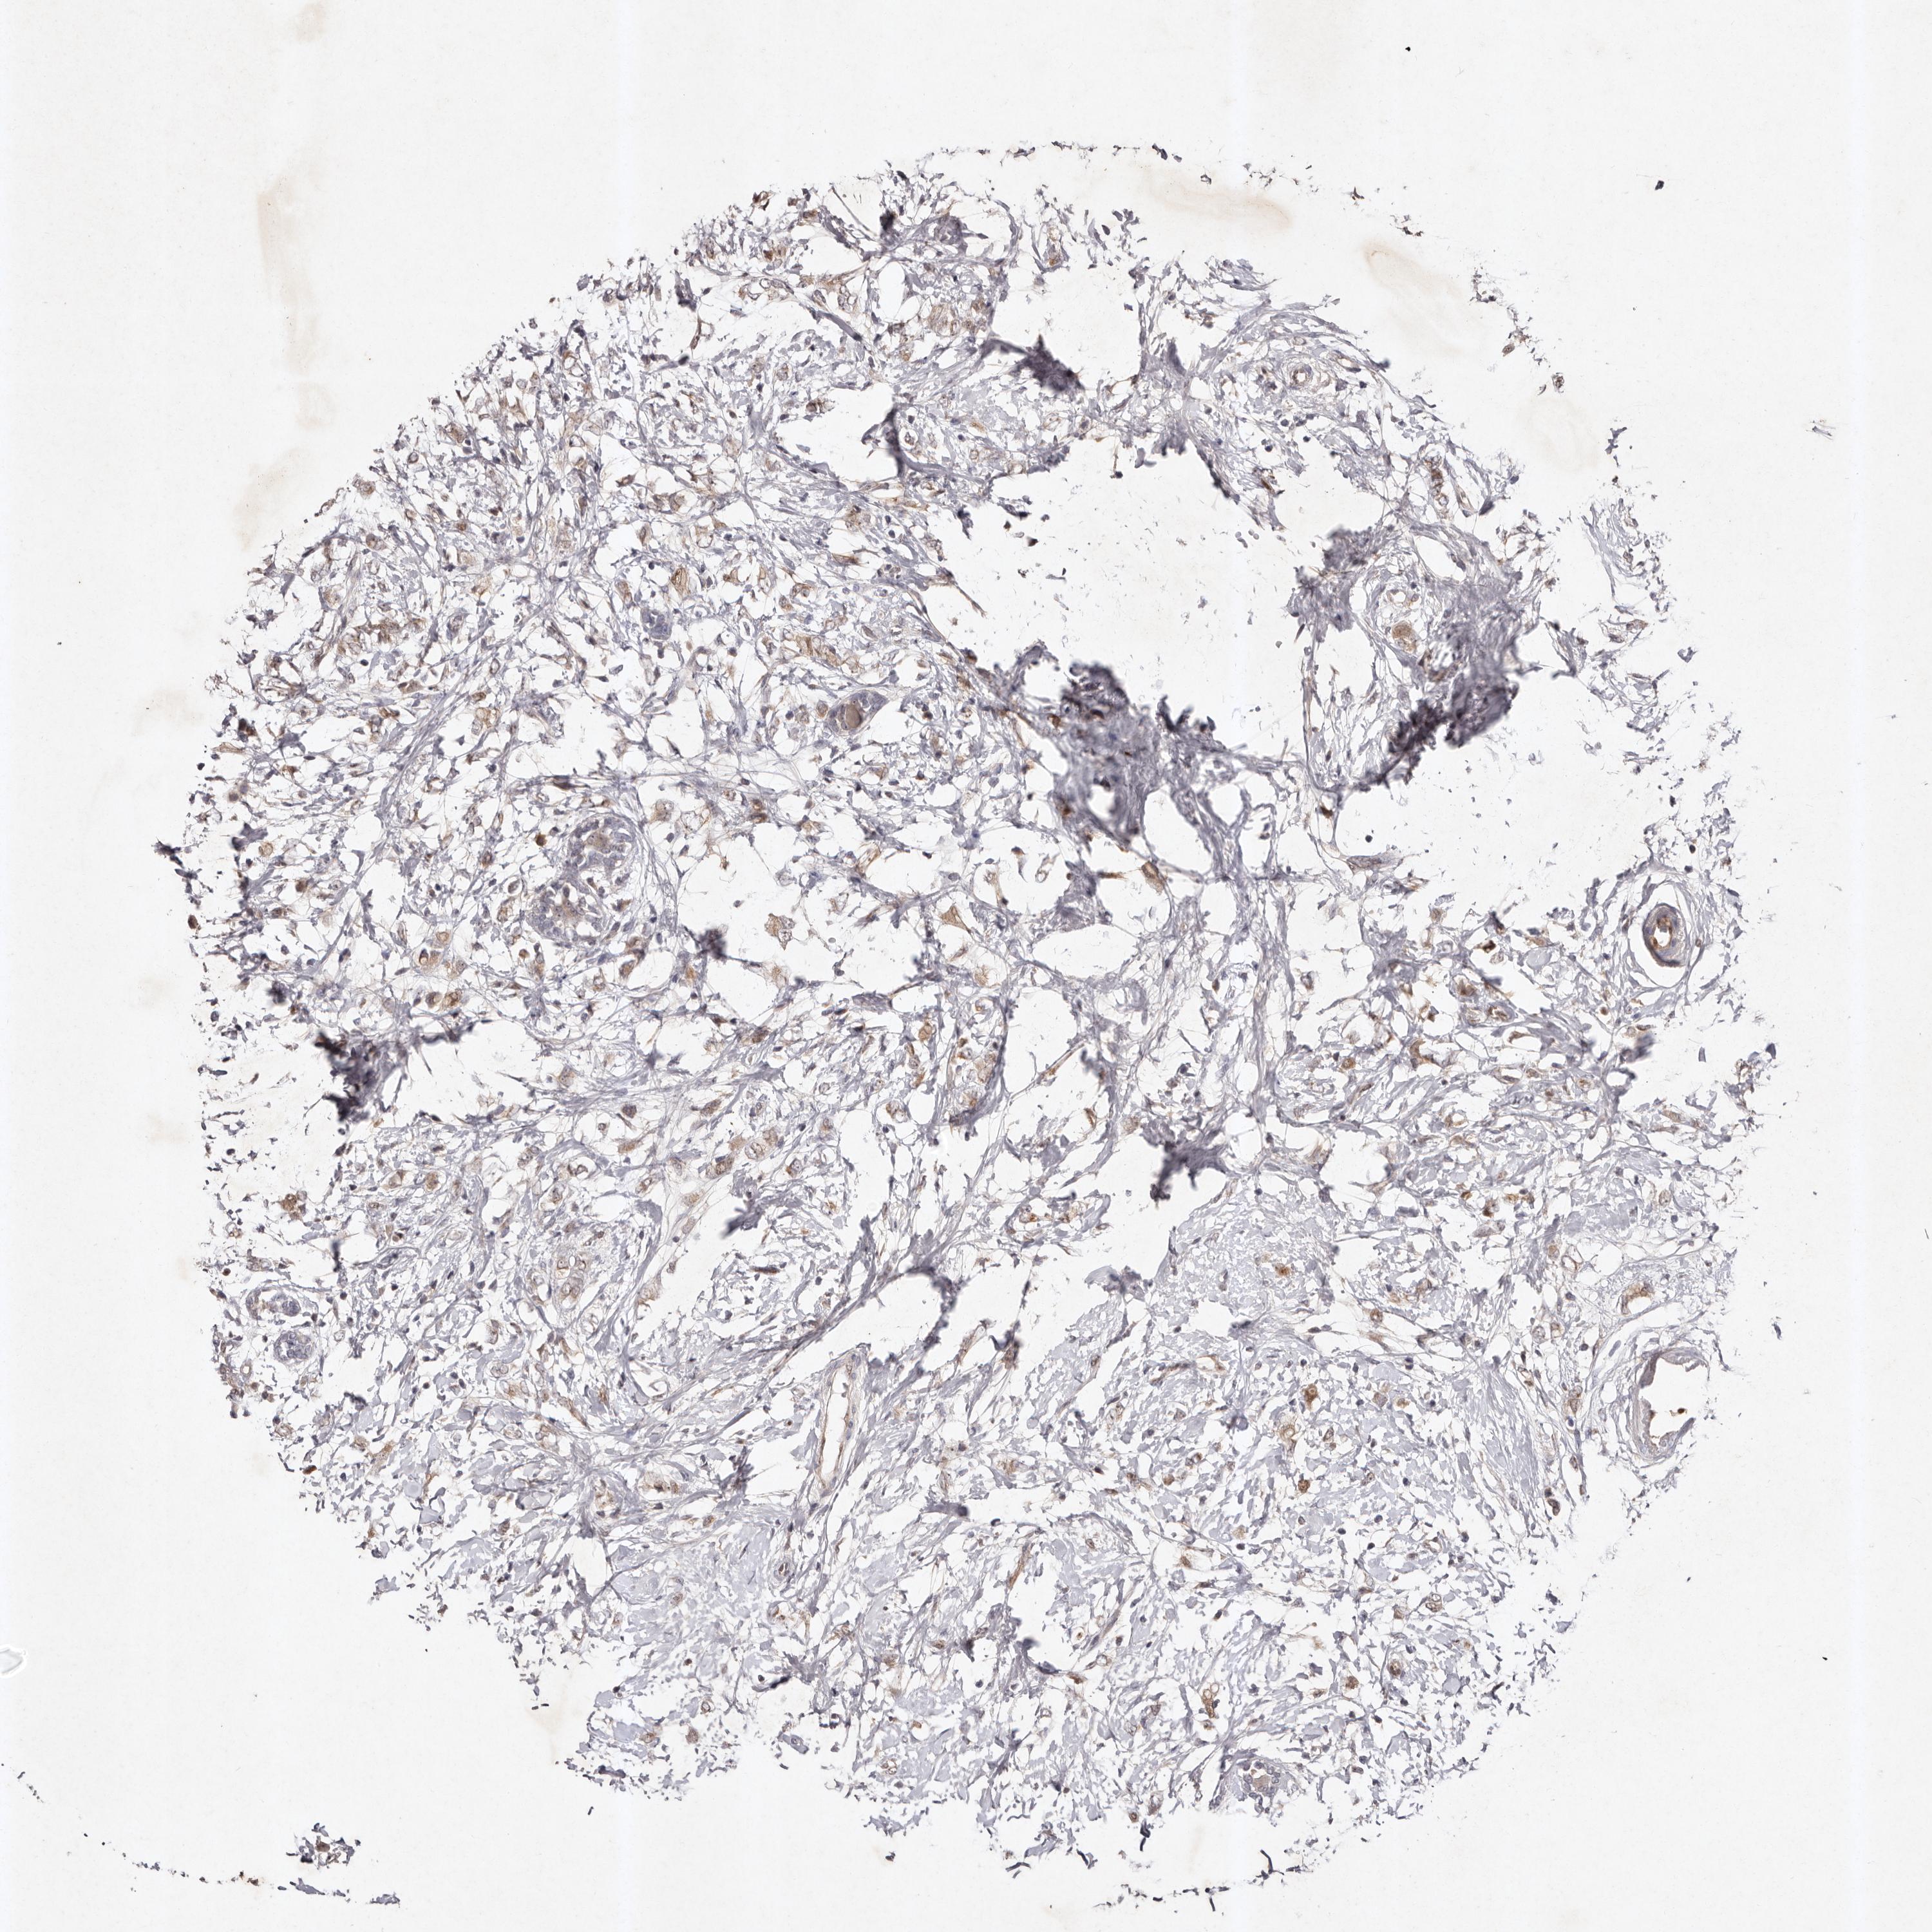

CANCER BREAST CANCER Show tissue menu

BRCA TCGA BRCA VALIDATION PROTEIN EXPRESSION